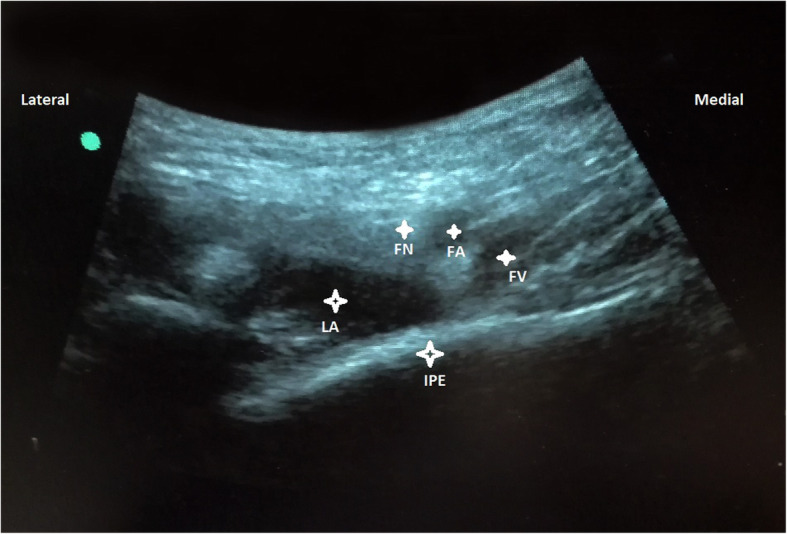

With the patients in supine position, a convex low-frequency (2–5 MHz) ultrasound probe was placed on a transverse plane over the AIIS and then it was aligned with the pubic ramus by rotating the probe counterclockwise at approximately 45 degrees. On this ultrasonographic view, the IPE, femoral nerve and vessels were clearly observed (Fig. 3). So with in-plane approach a 20-gauge and 100-mm needle was inserted from lateral to medial to place the tip in the musculofascial plane between the pubic ramus posteriorly and the psoas tendon anteriorly. Following negative resistence and aspiration tests, the local anesthetic solution composed of a mixture of mepivacaine 1% and ropivacaine 0,5% was slowly injected while observing for adequate fluid spread for a total volume of 20 mL (Fig. 4).

Fig. 4.

Femoral nerve (FN), artery (FA), vein (FV), Iliopubic eminence (IPE), Local anesthetic mixture (LA)